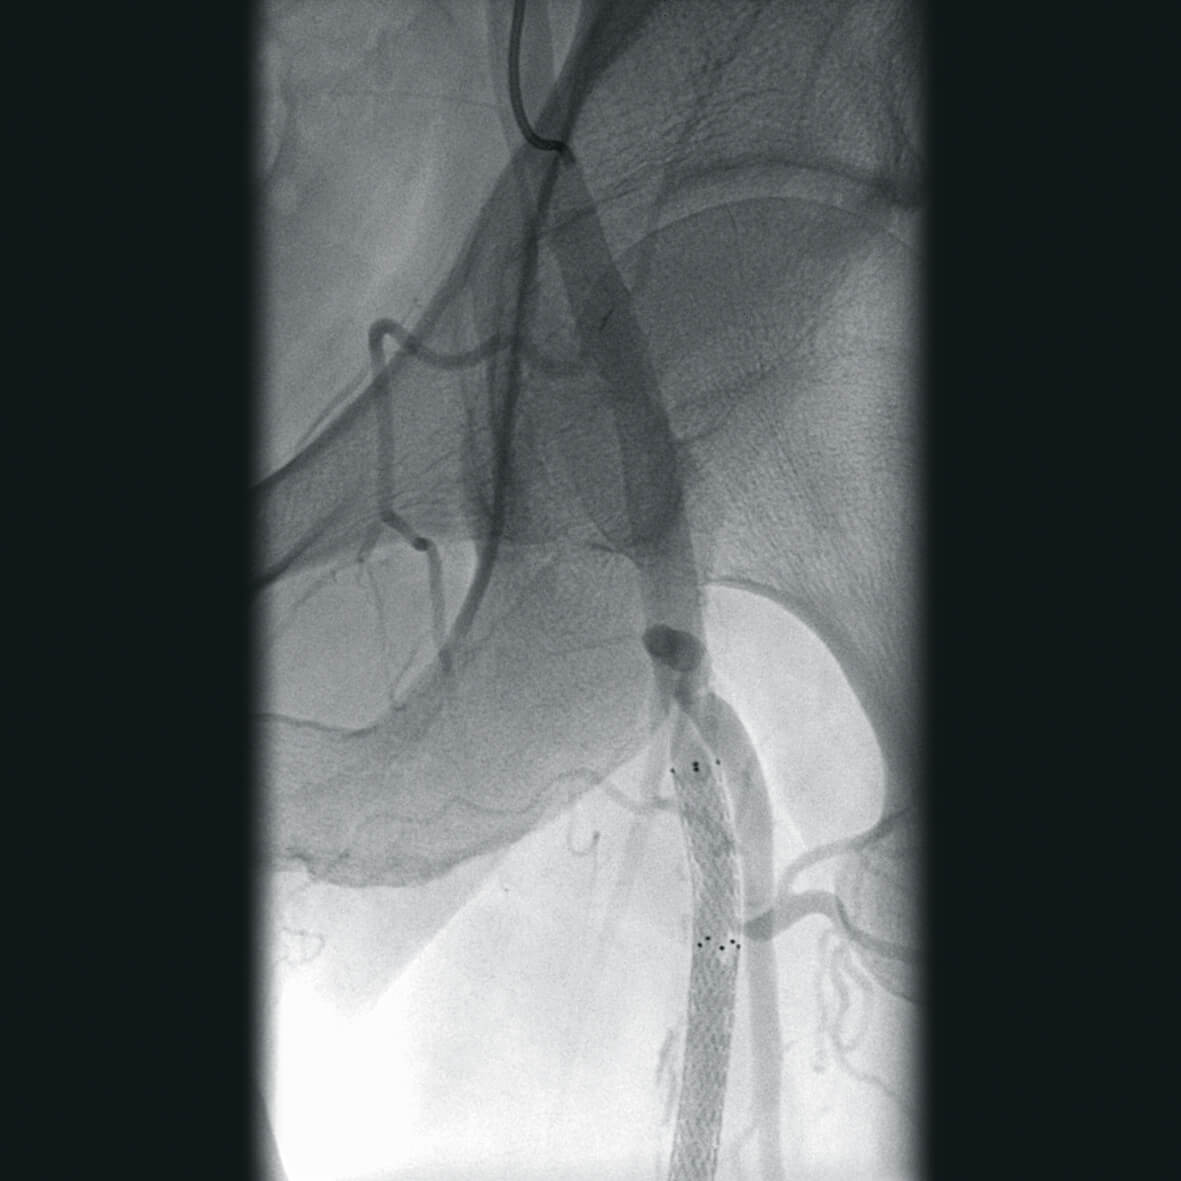

Полное отсутствие искажений снимков в сочетании с высоким динамическим диапазоном широко востребованы как при сложных операциях в нейрохирургии, сосудистой хирургии, инвазивной радиологии, так и в гибридных областях применения, а также в ортопедии, травматологии. В сосудистой хирургии особенно важны высокий динамический диапазон и пространственное разрешение, обеспечивающие детальную визуализацию даже мельчайших сосудов. Специализированное программное обеспечение SmartVascular позволяет проводить настройку системы для васкулярных операций и сосудистой хирургии.

Впервые в мировой практике в Vision RFD 3D используется невероятно компактный моноблочный генератор для импульсной рентгеноскопии с увеличенной резервной мощностью и вращающимся анодом рентгеновской трубки для улучшения качества изображений при минимальной интенсивности облучения. Продолжительность импульсов можно регулировать в диапазоне от 7 до 40 мс, что существенно повышает четкость снимков. Vision RFD 3D отлично подходит для использования в клинических процедурах типа: чрескожная транслюминальная коронарная ангиопластика или коронарная ангиография.